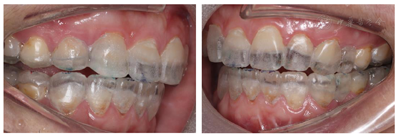

12、24、34、44牙缺失,12牙缺失牙间隙无,13牙与11牙建立邻接,24、34、44牙缺失牙间隙减少。咬合检查:上颌牙中线与面中线一致,下切牙中线右偏约1.5mm,11、13牙对刃,前牙部分开

,21、22、23、43牙与对侧牙无咬合接触,后牙有咬合,磨牙中性关系。余检查同术前(图8,图9,图10,图11)。